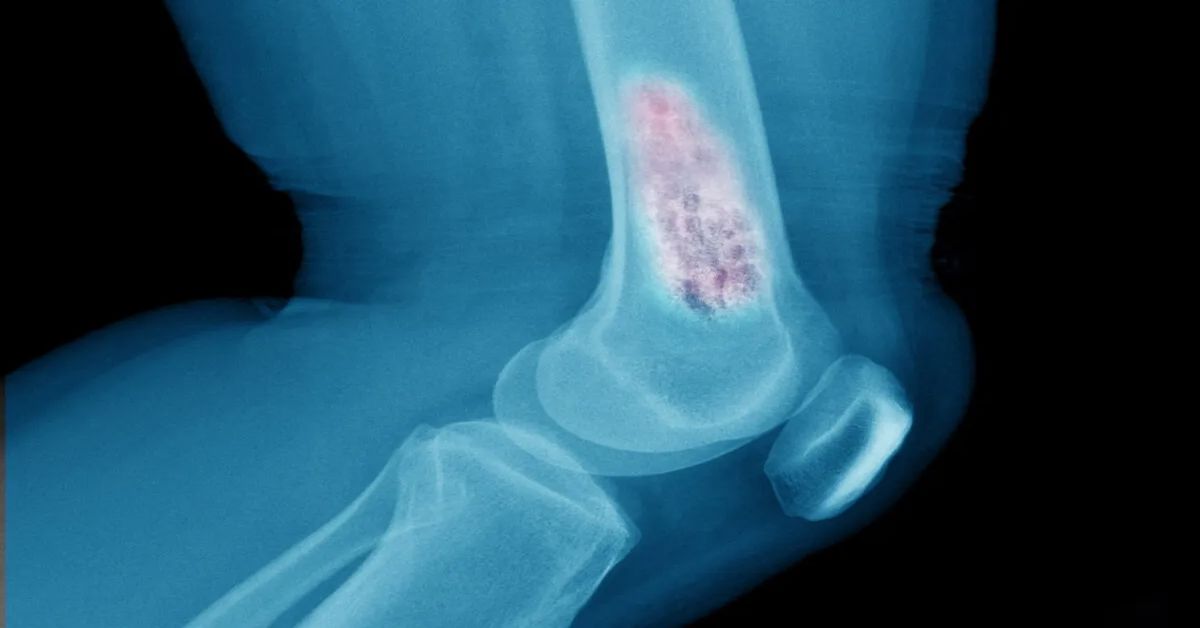

En sık görülen belirti şişliktir. Deri altında ele gelen kitle oluşur. Yumuşak doku tümörü durumunda bu kitle zamanla büyüyebilir. Ağrı her zaman görülmeyebilir. Ancak bazı hastalarda hassasiyet oluşur. Hareket sırasında rahatsızlık hissi artabilir. Kitle sert veya yumuşak olabilir. Bu durum tümörün yapısına bağlıdır. Belirtiler ciddiye alınmalıdır.

Yumuşak dokularda oluşan tümörler farklı yapıda olabilir. Kas yağ ve bağ dokusu etkilenebilir. Bazı tümörler iyi huylu olur. Bazı durumlar daha ciddi olabilir. Belirtiler zamanla ortaya çıkar. Şişlik en sık görülen bulgudur. Erken tanı önem taşır. Doğru tedavi planı süreci belirler. Uzman değerlendirmesi gereklidir.

Tedavi yöntemleri tümörün türüne göre belirlenir. Yumuşak doku tümörü durumunda cerrahi sık tercih edilir. Kitle tamamen çıkarılmaya çalışılır. Bu sayede yayılım riski azaltılır. Gerekli durumlarda ek tedavi uygulanır. Radyoterapi bazı hastalarda tercih edilir. Kemoterapi ileri vakalarda kullanılabilir. Tedavi süreci kişiye özel planlanır. Düzenli takip önem taşır.